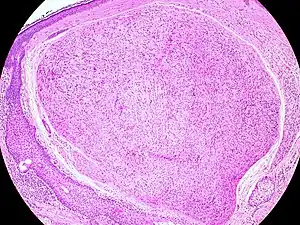

Palisaded encapsulated neuroma

| Micrograph of a palisaded encapsulated neuroma | |

Palisaded encapsulated neuroma (PEN) is a rare, benign cutaneous condition characterized by small, firm, non-pigmented nodules or papules.[1][2] They typically occur as a solitary (single) lesion near the mucocutaneous junction of the skin of the face, although they can occur elsewhere on the body.[3]

As mentioned previously, PEN is a benign, firm, flesh-coloured lesion that typically occurs in dermis of the skin of the face. The lesions are typically between 2–6mm and are slow-growing.[3][4]

PEN is diagnosed by clinical recognition of the lesion and on subsequent histologic examination. Typically, the lesions are suspected to be schwannomas or neurofibromas clinically with PEN being an incidental finding on histology.[3]

PEN is typically diagnosed in patients between the ages of 40 and 60 years and occurs more frequently in females than males. The diagnosis of PEN may be difficult, even with confirmatory histology, due to its histological similarities with schwannomas and neurofibromas. It is imperative that the correct diagnosis is made the misdiagnosis of a neurofibroma may lead to unnecessary further investigation into associated systemic syndromes such as neurofibromatosis type 1 or multiple endocrine neoplasia syndrome.[3][4]